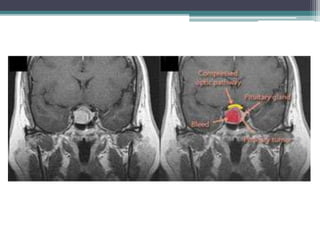

• Involvement of the chiasm is suggested by visual loss of any type associated with pituitary

dysfunction or by a monocular or bitemporal hemianopia.

• Compressive chiasmal lesions typically cause gradual decline in vision, as they impinge

upon the chiasm, optic nerve, or optic tract. Peripheral vision loss is often asymptomatic

until visual acuity is compromised; therefore, most visual complaints are of gradual

blurring or dimming of vision. Sudden chiasmal vision loss is less common and

implies a rapidly expanding mass or an infectious, vascular, or inflammatory

cause.

• Ophthalmic examination may reveal optic disc pallor if the process is longstanding. Optic

disc swelling may result from papilledema (with third ventricle obstruction) or from an

infiltrative or inflammatory process.

• Chiasmal visual field defects classically involve the temporal fields and respect the vertical

midline in one or both eyes. Defects of ocular motility, due to palsies of the third, fourth, or

sixth cranial nerve, may accompany chiasmal lesions that extend into the cavernous sinus.

• Pituitary apoplexy is relatively rare, occurring predominantly in patients with preexisting

adenoma Emergency steroid and other hormonal replacement, and/ortranssphenoidal

surgery, is often indicated. The clinical syndrome is characterized by the acute onset of

visual loss, headache, ophthalmoplegia, and altered mental status due to hemorrhage or

infarction of the pituitary gland, resulting in rapid expansion into the suprasellar space and

cavernous sinuses. Clinical suspicion mandates MRI, as CT may miss the lesion